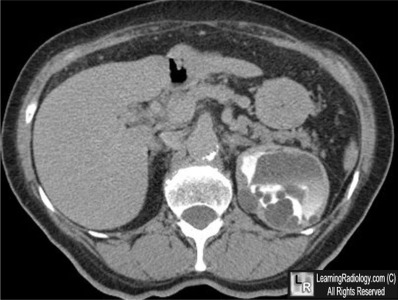

Additional Image - Axial contrast-enhanced CT of the upper abdomen

Axial contrast-enhanced CT of the upper abdomen

4. Cystic Nephroma

Cystic Nephroma

• Rare, unilateral multi-loculated cystic tumor lacking blastemal elements

• Solitary, well-circumscribed

• Non-communicating fluid-filled locules, surrounded by thick, fibrous capsule

• Do not connect to the collecting system

• Usually quite large (mean 7.6 cm by 9.7 cm)

• Most common in lower pole